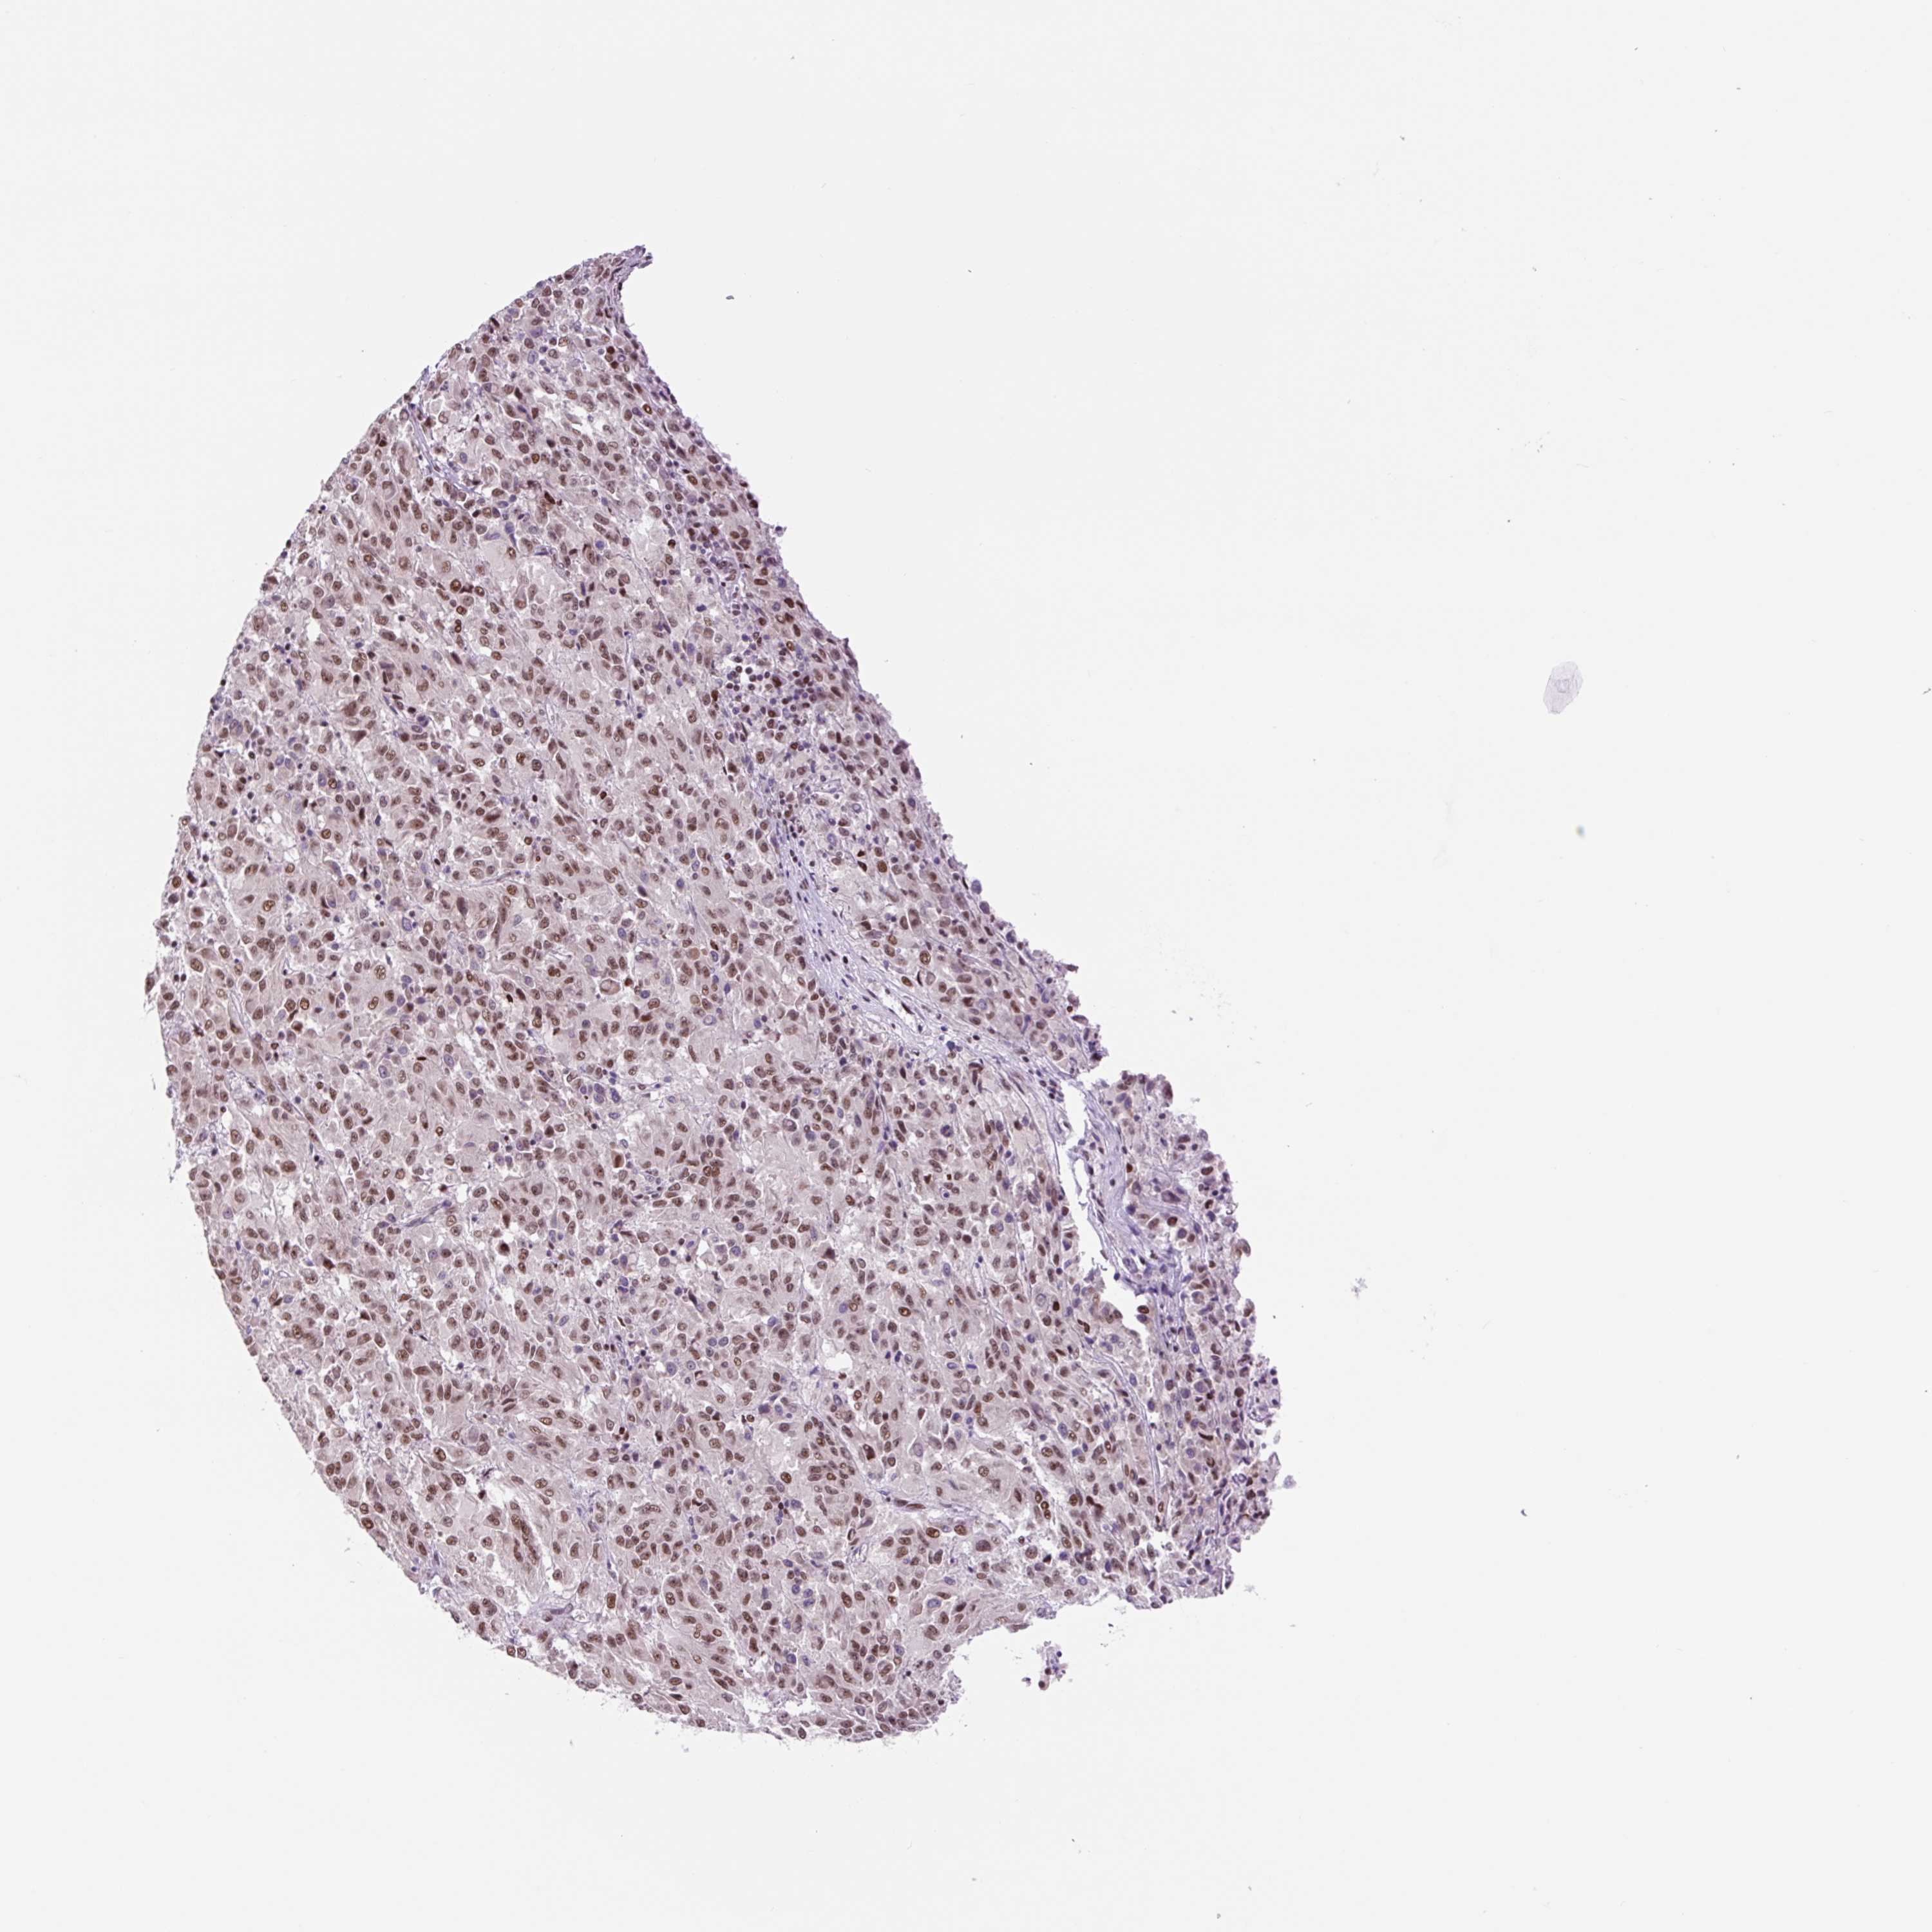

MELANOMA - Protein expressioni

A mouse-over function shows sample information and annotation data. Click on an image to view it in a full screen mode. Samples can be filtered based on level of antibody staining by selecting one or several of the following categories: high, medium, low and not detected. The assay and annotation is described here.

Note that samples used for immunohistochemistry by the Human Protein Atlas do not correspond to samples in the TCGA dataset.

Antibody stainingi

Antibody staining in the annotated cell types in the current human tissue is reported as not detected, low, medium, or high, based on conventional immunohistochemistry profiling in selected tissues. This score is based on the combination of the staining intensity and fraction of stained cells.

Each image is clickable and will lead to virtual microscopy that enables deeper exploration of all samples and also displays staining intensity scores, fraction scores and subcellular localization as well as patient and tissue information for each sample.

Antibody HPA054334

Staining

High

Medium

Low

Not detected

Intensity

Strong

Moderate

Weak

Negative

Quantity

>75%

75%-25%

<25%

None

Location

Nuclear

Cytoplasmic/membranous

Cytoplasmic/membranous,nuclear

Malignant melanoma, NOS

Malignant melanoma, Metastatic site